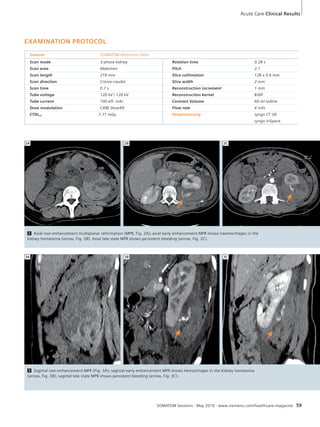

(Fig. 7B) and there was also an im-provement

in the neurologic exam,

specifically in the left facial palsy. The

patient was discharged on day 17, neu-rologically

stable with resolution of the

facial droop, well-controlled pain and

ambulating without assistance. She was

scheduled for a follow-up exam in the

clinic 6 weeks later.

COMMENTS

syngo VPCT Neuro offers dynamic perfu-sion

analysis of the entire brain. That,

as in this case, enables the detection of

vasospasms – even those located in

upper brain regions or in the posterior

fossa, not covered by traditional Perfu-sion

54 SOMATOM Sessions · May 2010 · www.siemens.com/healthcare-magazine

CT through the base of skull. Thus

syngo VPCT Neuro in combination with

the Adaptive 4D Spiral technology is en-hancing

the diagnostic application. The

ability to obtain a CT Angiography with

the same data acquisition is crucial for

the correlation to the vascular territory

showing prolonged MTT. Temporal pa-rameter

maps like MTT in 2D and 3D

delivered by syngo VPCT Neuro may act

as a sensible tool to detect perfusion

asymmetries in the two hemispheres as

an indicator for vasospasm.

5